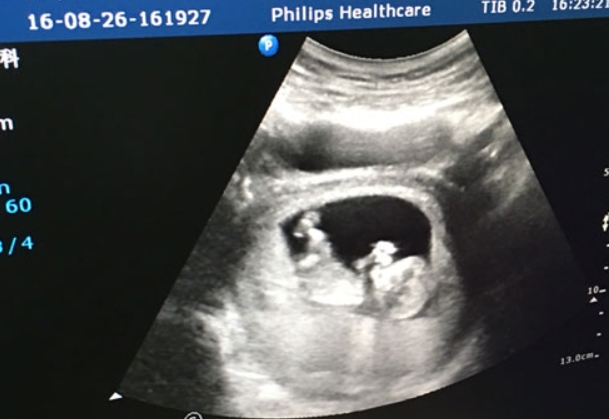

刚拿到NT报告的准妈妈小陈盯着单子上的「1.2mm」直犯嘀咕:网上都说NT值要<2.5mm,那我这个是不是太小了?诊室外的对话更让她焦虑——隔壁孕妇正炫耀自己「0.8mm的超低值」。这种场景在产科门诊几乎每天都在上演,但NT值真的是越小越优秀吗?让我们用数据和事实来说话。一、揭开NT检查的神秘面纱这个让准爸妈们紧张兮兮的NT检查,说白了就是通过B超测量胎儿颈后部透明层的厚度。就像给新生儿测黄疸值一

孕11周nt值3.4胎儿染色体异常的风险可能比较高。在孕早期进行的NT(颈后透明带)检查是用于筛查胎儿是否有染色体异常,如唐氏综合症的常规检测指标之一。NT值是胎儿颈部透明带的厚度,通常在怀孕11-14周之间测量。一般来说,NT值的正常范围是在1.5-2.5mm,如果nt值大于3.0毫米,可能增加胎儿染色体异常的风险。然而,NT值的增厚并不一定等于诊断结果,建议进行进一步检查。NT检查是通过测量胎